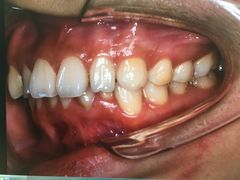

• 固瑞齿科(国贸门诊店)

• -固瑞齿科(国贸门诊店)

点小评4457552211 | 18-12-31

报错